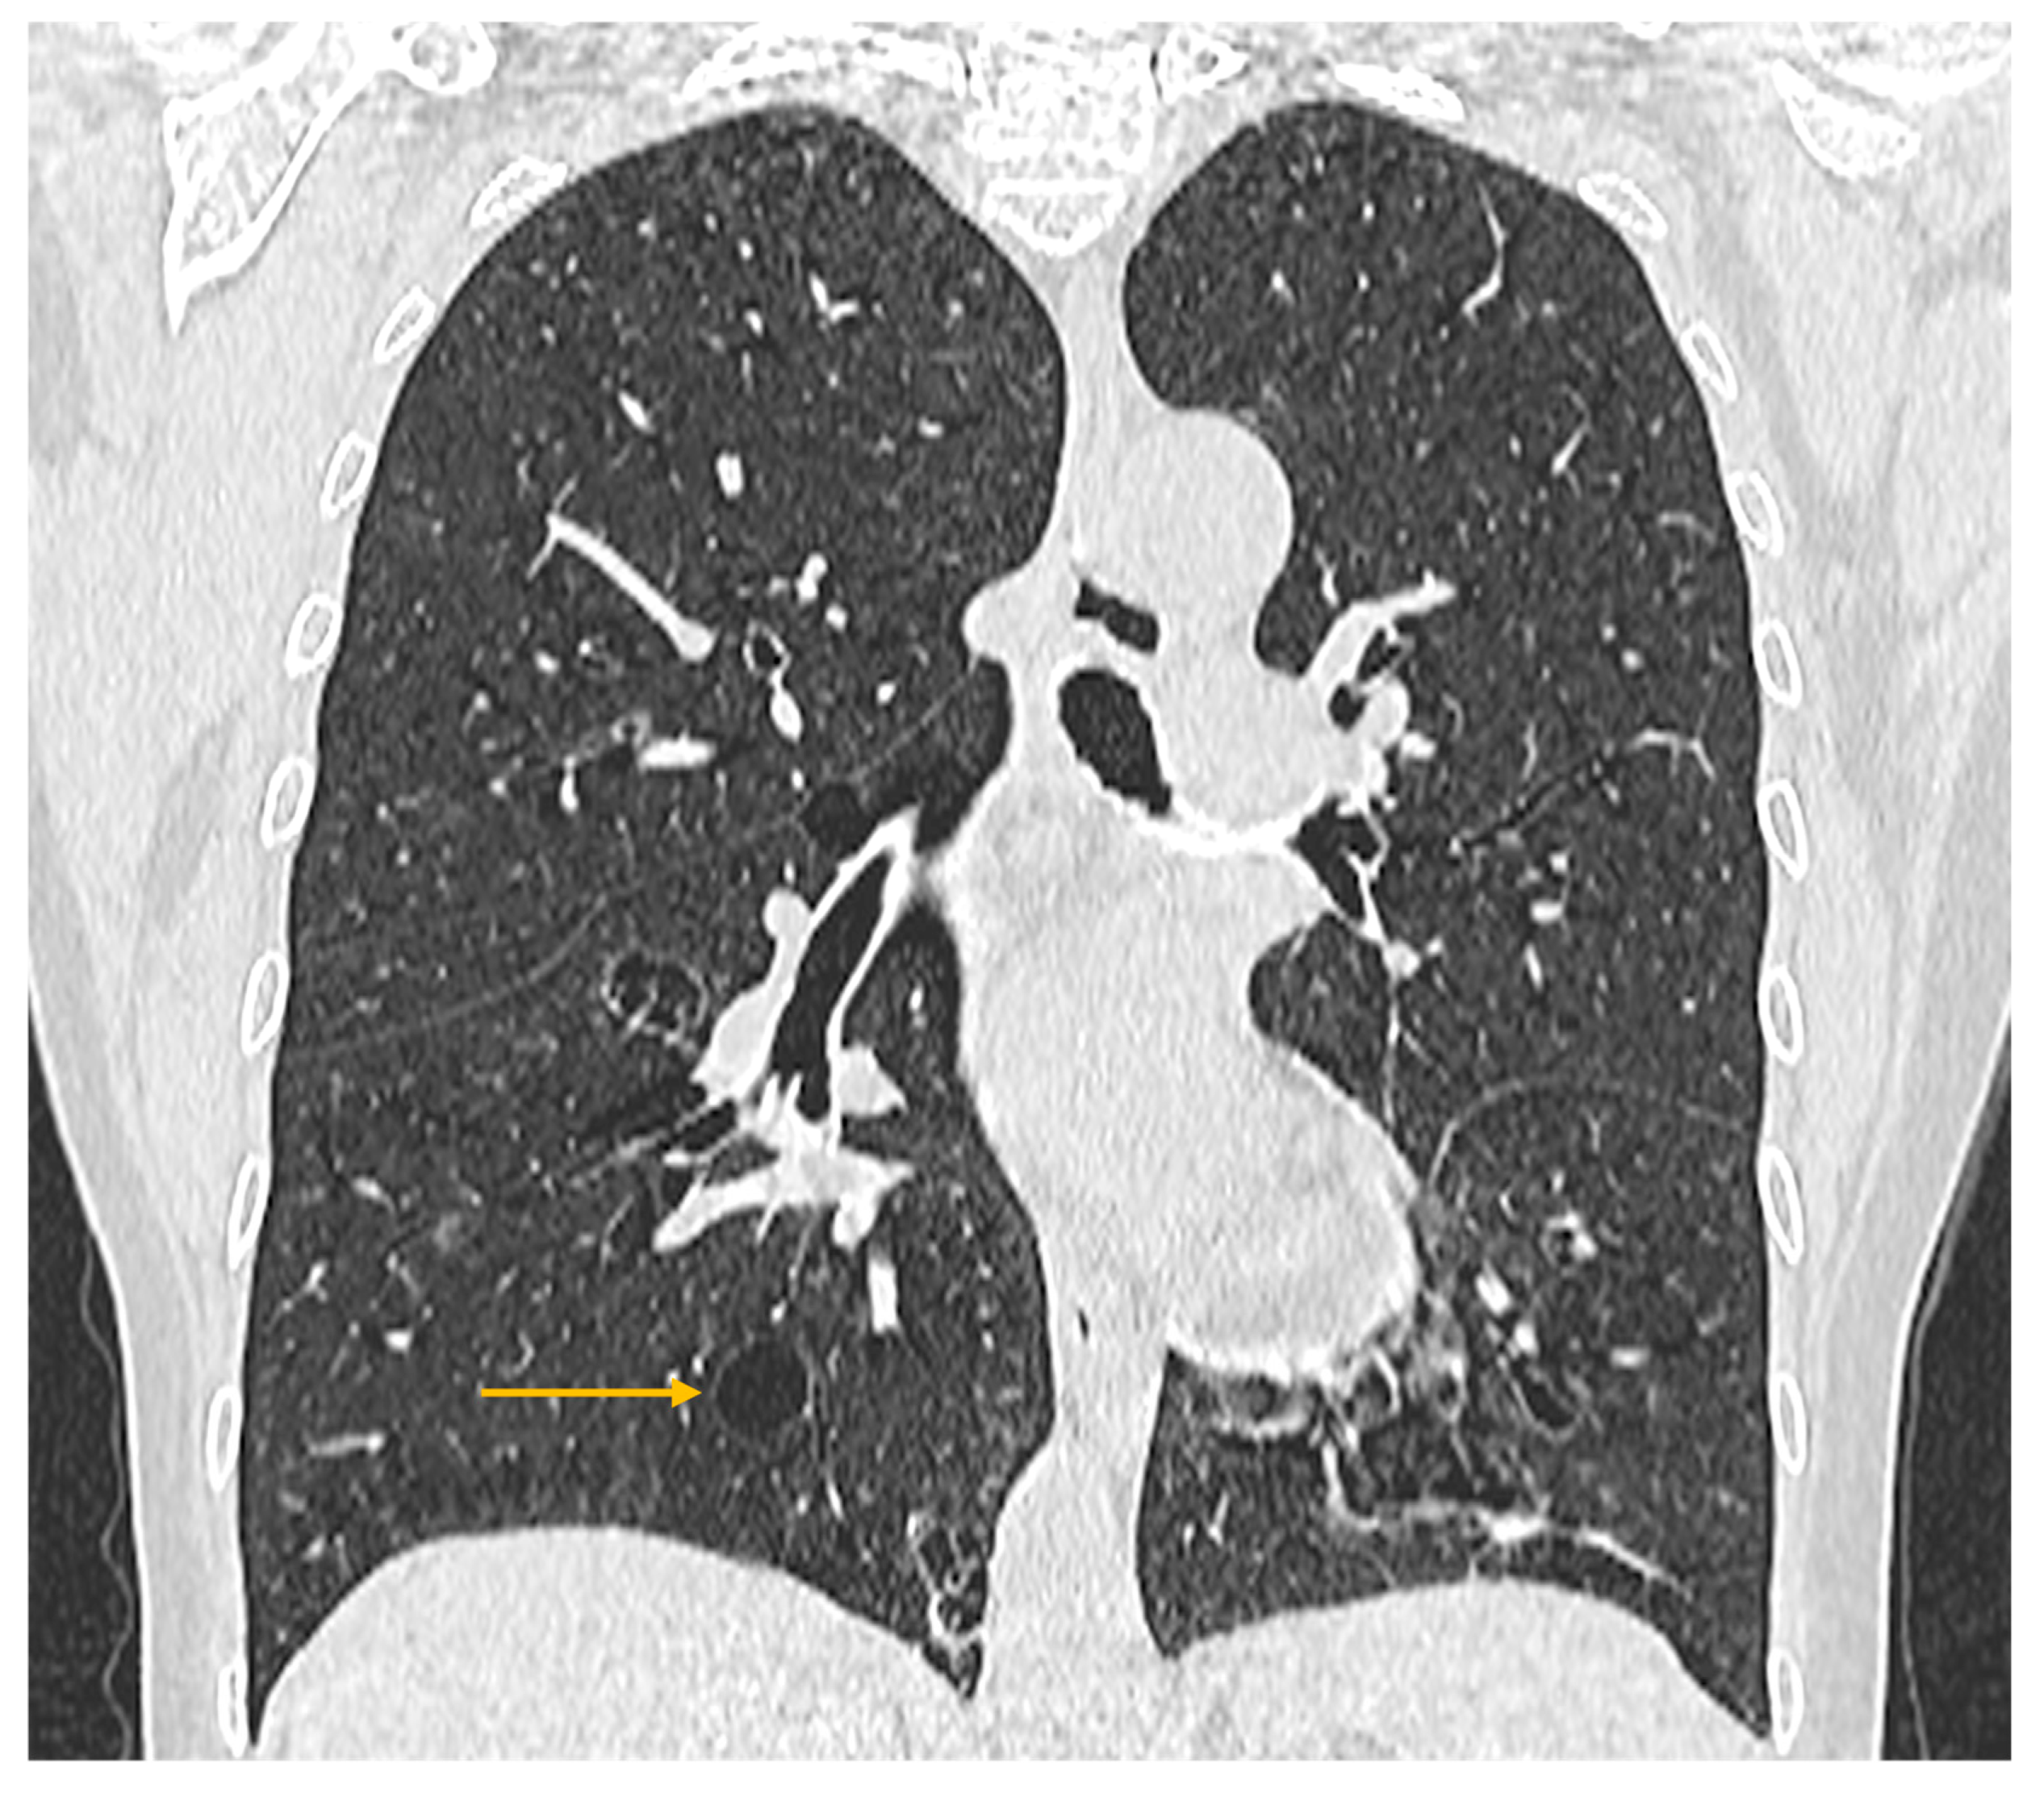

Figure 5. High-resolution computed tomography (HRCT) of the chest in lymphocytic interstitial pneumonia (LIP). Coronal HRCT image demonstrates thin-walled pulmonary cysts (arrow), a characteristic imaging feature of LIP.